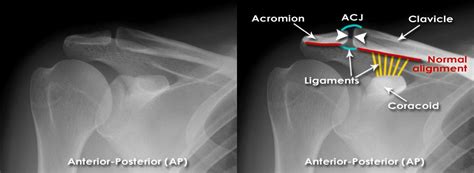

Acromioclavicular Joint X Ray

Struggling with an AC joint sprain? Discover effective treatment options, recovery timelines, and physical therapy exercises to manage shoulder pain. Learn how to diagnose a separated shoulder, reduce inflammation, and regain mobility safely. Our comprehensive guide helps you understand the grades of injury and provides essential steps for a successful, pain-free recovery and long-term shoulder joint health.